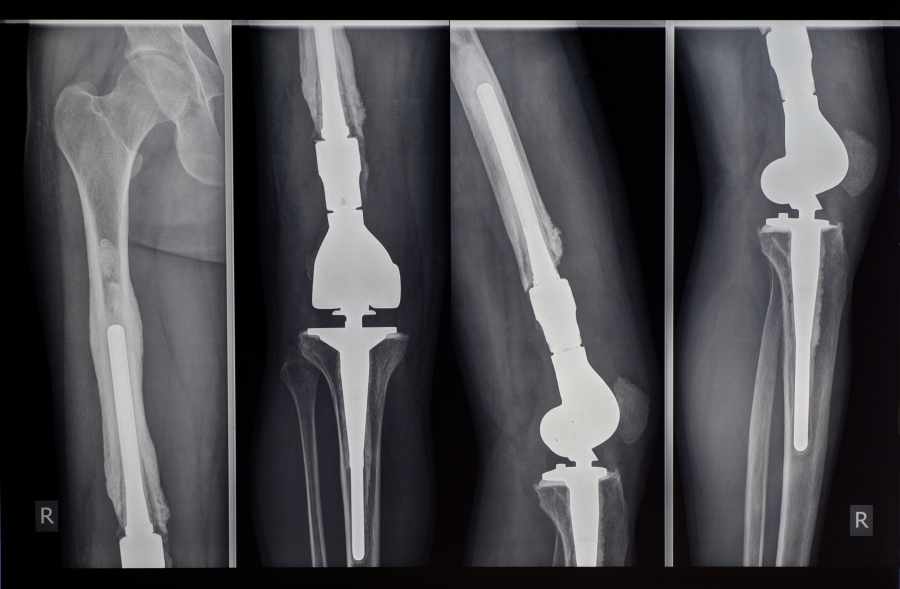

A KNEE-T JOB

As upgrades improve their efficacy, computer-assisted knee surgeries are helping those with arthritic or damaged joints get back on their feet, often on the same day as the procedure

Albert Colaco, 84, says being able to stand, walk, sleep and cycle again is nothing less than a miracle. Diagnosed with severe osteoarthritis in both knees, he could barely walk 50 metres at a stretch until eight months ago, when he underwent computer-assisted total knee replacement surgery at Mumbai’s Jaslok Hospital.

He was able to stand the same day and was discharged on day four. His surgeon Dr Ameet Pispati attributes this, in part, to the fact that the surgery was computerised-surgery.

“At Colaco’s age, operations are usually risky. But since all his vitals — blood pressure, sugar and haemoglobin levels — were normal, we decided to go ahead,” he says. “Because it was a computerised surgery, he was able to recover quickly and resume his routine.” Orthopaedic surgeons across India are finding that, as the technology improves, computer-assisted surgeries are offering even greater benefits to patients — benefits that have also been outlined in a 2015 study that analysed 57 knee replacement cases at Delhi’s All India Institute of Medical Sciences (AIIMS).

“Computer-assisted surgeries are not only more accurate but also safer. Additional benefits include shorter hospital stays, less blood loss and a reduced risk of post-surgery complications,” says Dr Rajesh Malhotra of the AIIMS orthopaedics department, who led the research team.

The study, which was published in the Journal of Bone and Joint Surgery, explored how computerisation reduced the risk of life-threatening clot formations that sometimes resulted from the cutting of the bone as done in conventional surgery.

“In a computerised surgery, surgeons can cut the bone at accurate angles and balance the soft tissue around the knee area. This helps in achieving better knee alignment too,” adds Dr Tejas Upasani, a Mumbai-based orthopaedic surgeon. “It also quantifies the tension around the ligament to help the doctor decide how much ligament release should he apply.”This kind of advancement is also encouraging patients to overcome their fear and go under the knife to improve their quality of life.

Delhi-based artist Manu Parekh, 76, for instance, opted for a knee replacement after an x-ray revealed that his arthritis had reached an advanced stage. “Driving had become very painful,” says Parekh. “So had standing for long hours, which I need to do daily to complete my paintings.”His condition was bad; the only way to improve his quality of life was to have both his knees replaced, says Dr Rajgopal, chairman of Medanta Hospital’s Bone and Joint Institute. Today, as a result of the surgery, Parekh is up on his feet, walking, painting and travelling again. “Studies have indicated that more than 90% of patients who have had total knee replacement surgery experience dramatic reductions in knee pain and a significant improvement in the quality of life,” adds Dr Rajgopal. “This is even more true for those undergoing computerised knee replacement surgery.”

“The shelf life of an implant in a knee replacement procedure depends on how well the implant is aligned with the bone. The gyroscope technique helps immensely in this,” says Dr Yash Gulati, senior orthopaedic and joint reconstruction surgeon at the hospital.

While this is a case of a new kind of computerised equipment, similar degrees of improvement are coming to knee surgery via software upgrades. “The basic principle usually stays the same,” says Dr Malhotra of AIIMS. “The aim is to ensure that the implant is as well-aligned with the bone as possible. And different machines with their improved software are helping us achieve this alignment to a greater degree than ever before.”